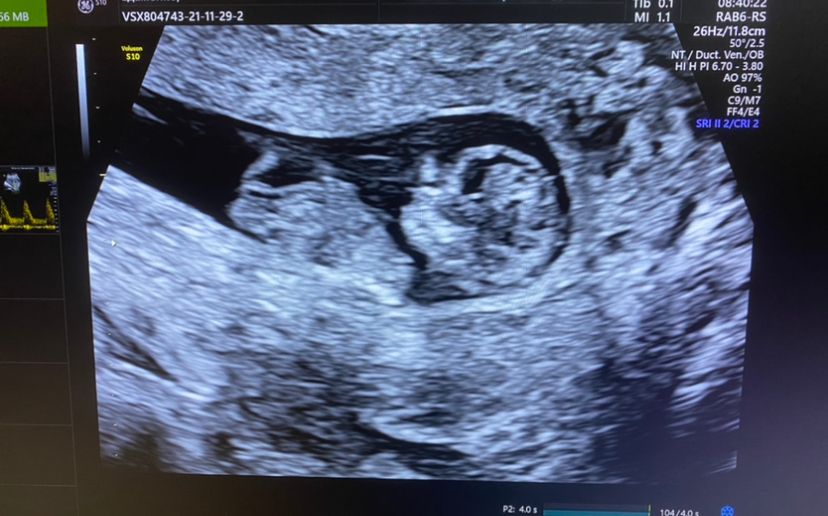

Первый скрининг

Девочка. Вряд-ли это парень)

Поздравляю вас♥️ очень похоже на девочку🤗

Оля, тоже хочу девочку, а на первом скрининге не смогли предположить сильно вертелся малыш😅 пойду ещё в 16 недель на УЗИ специально пол посмотреть, что б к новому году уже знать🎄 Но по вашему снимку, как уже и говорила скорее всего девочка♥️